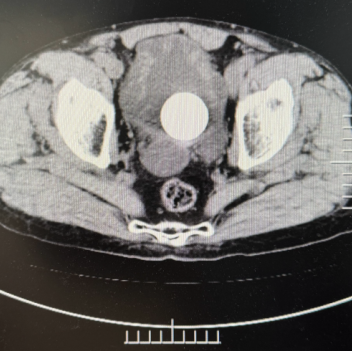

宋健教授作为泌尿外科领域专家,在接到魏叔叔病历后,立即对其病情进行了全面细致的评估,魏叔叔不仅前列腺增生较重,而且膀胱内结石达4x4cm,凭借着丰富的临床经验和深厚的专业知识,宋健教授为患者制定了一套个性化的治疗方案。手术过程中,宋健教授、外科团队、手麻团队默契配合,用等离子电切刀剜除了增生的前列腺组织,采用钬激光碎石技术,将结石击碎后从尿道取出,手术成功完成。

膀胱结石